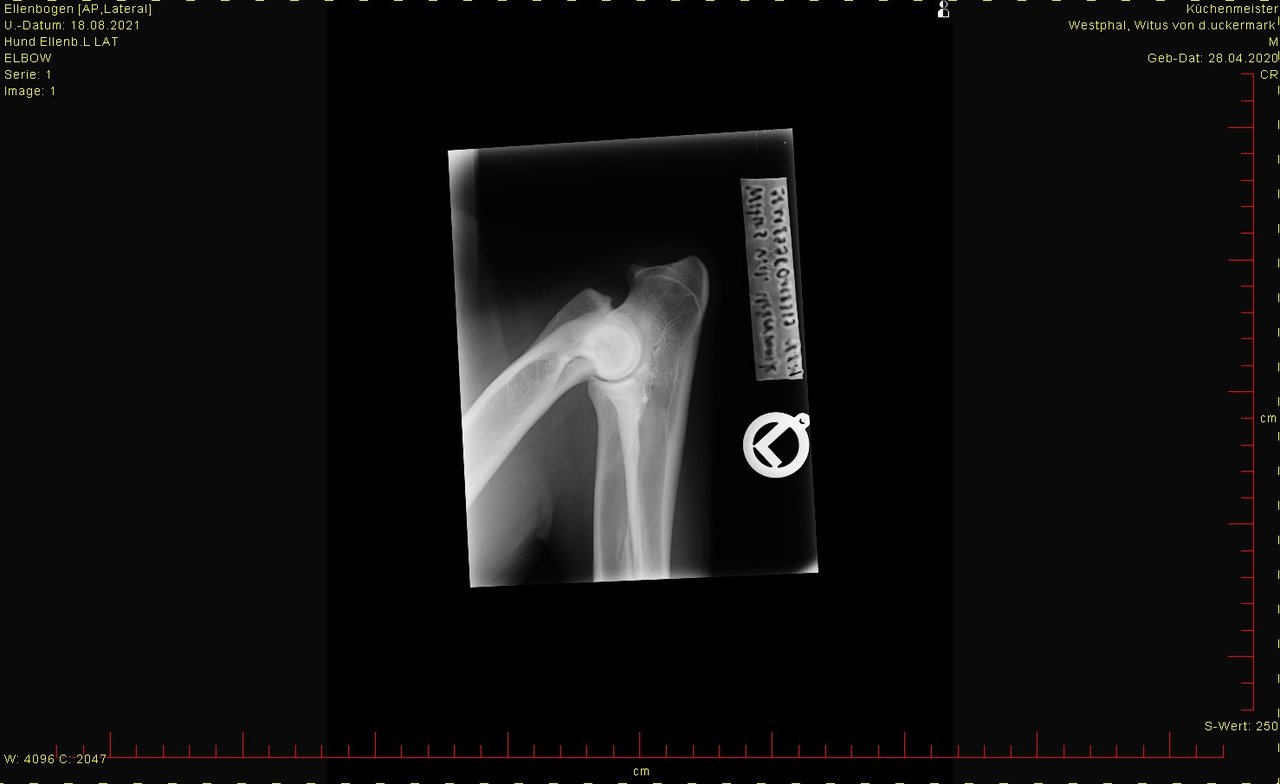

ED hat er nicht, LÜW sah auch ok aus.

Bei den Ellenbogen traue ich mir keine Bewertung zu, finde aber, dass Hüfte und Rücken okay sind